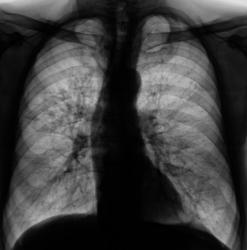

Пациент был направлен на рентгенологическое исследование органов грудной полости с диагнозом - "Пневмония?". Произведено стандартное исследование. Было решено провести противовоспалительное лечение, после которого провести "рентген-контроль".

После проведения противовоспалительного лечения проведен рентген-контроль.